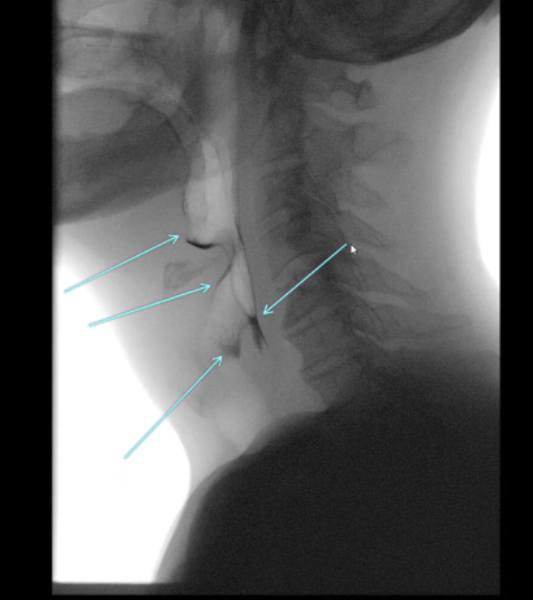

Pre-swallow Residue

Quick Takeaways

Data obtained when using the ASPEKT-C Method.

Steps for Completion

Record the presence of residue at the beginning of a clip, prior to new material entering the oral cavity.

Note: Compared to clean baseline swallows, those with pre-existing (pre-swallow) residue exceeding consistency-specific thresholds were associated with approximately twice the likelihood of an “atypical” PAS score (≥3) on that swallow (Steele et al., 2020).

Example: Use of telestrations in TIMS MVP to point out pre-swallow residue.